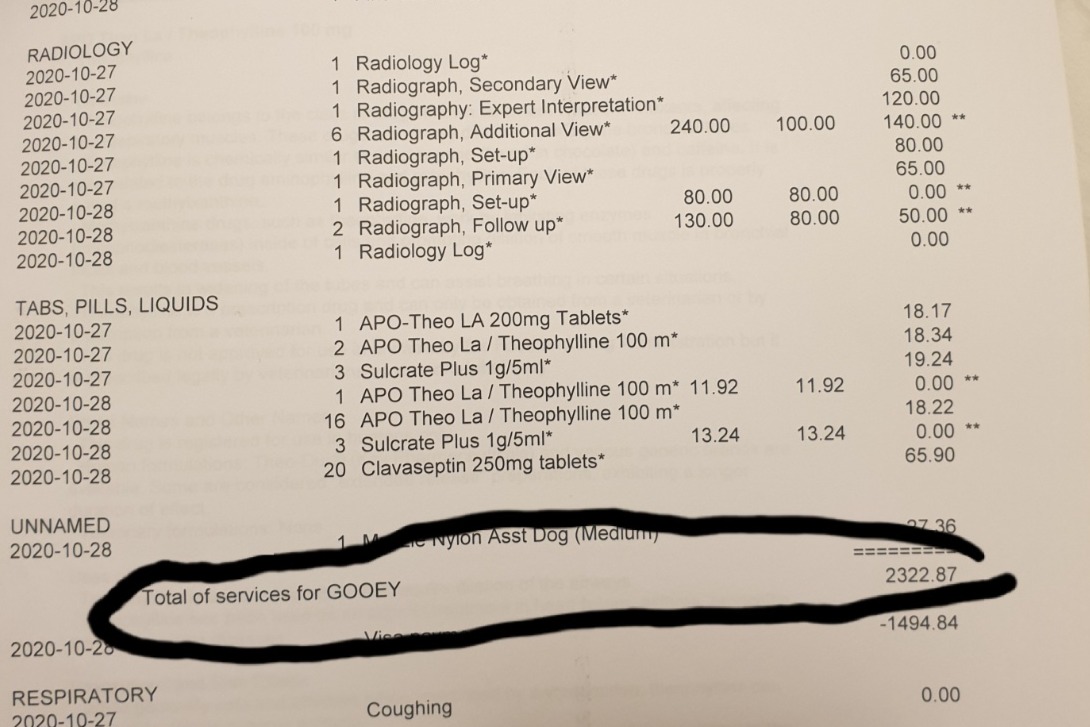

Gooey, Male.Gooey has been my best friend for 4 years, I got him since he was still a 3.5mths puppy, I brought him with me on the plane from Indonesia. While it is also the first time with me arriving in Canada. We going through a lot of difficulties together, while this pandemic also make everything more difficult for us. Right now his vet bills totalled $3401.

I have peoples donated to me directly totalled $1120. So I just need a little bit more kindness from all of you, please.